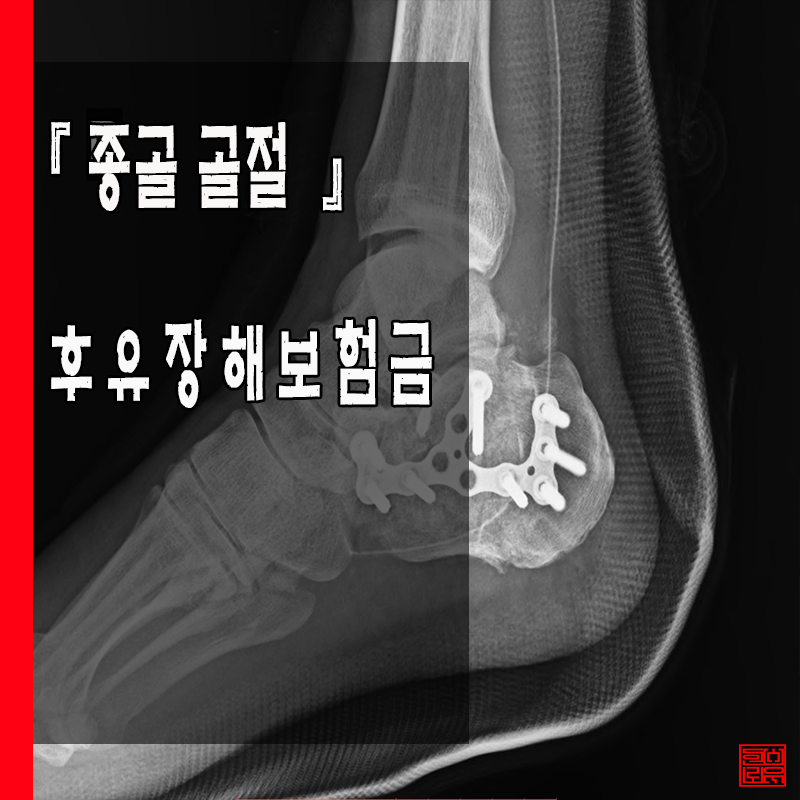

Á¾°ñÀº °ÉÀ¸¸é¼ »ç¶÷ÀÇ ¹«°Ô¸¦ Áö¸éÀ¸·ÎºÎÅÍ ¸¹ÀÌ ¹Þ´Â ºÎºÐÀÔ´Ï´Ù. µû¶ó¼ °æ¿ì¿¡ µû¶ó ³ôÀº °÷¿¡¼ ¶³¾îÁö°Å³ª ȤÀº °ÇÑ Ãæ°ÝÀ» ¹ÞÀ¸¸é Á÷¾Ð¹Ú·ÂÀÌ À§·Î Àü´ÞµÇ¾î ôÃß¾Ð¹Ú °ñÀý¿¡ À̸£±â±îÁö ÇÕ´Ï´Ù. Á¾°ñÀº °ÉÀ»¶§ Ãæ°ÝÀ» ¸¹ÀÌ ¹Þ´Â ºÎÀ§ À̹ǷΠµµº¸½Ã »ó´çÇÑ ÅëÁõÀÌ ¿Ã¼ö ÀÖ´Â ºÎÀ§À̸ç, À§Ä¡·Î´Â ¹ß µÚ²ÞÄ¡ »ÀÀÔ´Ï´Ù. »À°¡ µÎÅÓ°í Å« ±¸Á¶¸¦ À̱⿡ ½±°Ô ¼Õ»ó°¡°Å³ª °ñÀýµÇÁö ¾Ê´Â ºÎÀ§À̱⵵ ÇÕ´Ï´Ù. °ÅÀÇ ´ëºÎºÐ Ãß¶ô»ç°í½Ã °ñÀýµÇ´Â ºÎÀ§ À̸ç ÀÌ·²°æ¿ì ºÐ¼â°ñÀýÀÇ ÇüŸ¦ ¶ç´Â °æ¿ì°¡ ¸¹¾Æ ¼ö¼úÀ» ÇØ¾ßÇÏ´Â °æ¿ì°¡ »ó´çÇÏ¸ç »óŰ¡ È£ÀüµÇ±â±îÁö´Â »ó´çÇÑ ½ÃÀÏÀÌ ÇÊ¿äÇÑ Áß¿äÇÑ ºÎÀ§¶ó°í ÇÒ ¼ö ÀÖ½À´Ï´Ù.

K¾¾´Â 0000³â 0¿ù 0ÀÏ, ¾à 3M ³ôÀÌ »ç´Ù¸®¿¡¼ Ãß¶ôÇÑ »ç°í·Î 00º´¿ø ÀÀ±Þ½Ç°æ¿ì, ÁÂÃø Á¾°ñ °üÀý³» ºÐ¼â°ñÀý ¹× ¼ö¼úÈÄ ¿°Áõ ¹× °ñ¼ö¿° Áø´ÜÇÏ¿¡ ÁÂÃø °üÇ÷Àû Á¤º¹¼ú ¹× ±Ý¼ÓÆÇ °íÁ¤¼ú ½ÃÇà¿´°í, ±Ý¼ÓÆÇÁ¦°Å¼úÀ» 00³â 0¿ù 0ÀÏ º´¿ø¿¡¼ ½ÃÇàÇÏ¿´½À´Ï´Ù. ÀÌÈÄ ÇǺΠ¹× ¿¬ºÎÁ¶Á÷ ±«»ç¿¡ ´ëÇÑ ÇÇÆÇÀ̽ļúµµ ÀÌÈÄ ½ÃÇàÇÏ°Ô µÇ¾ú½À´Ï´Ù.